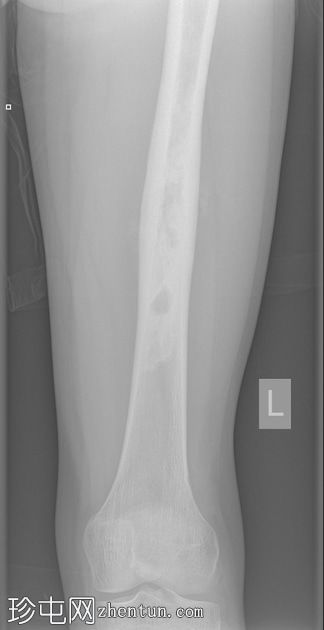

X光片

正面

左股骨中段可见边界不清的硬化区域,伴有宽阔的过渡区和虫蛀状外观。

邻近软组织可见小块钙化灶。无骨折或脱位。